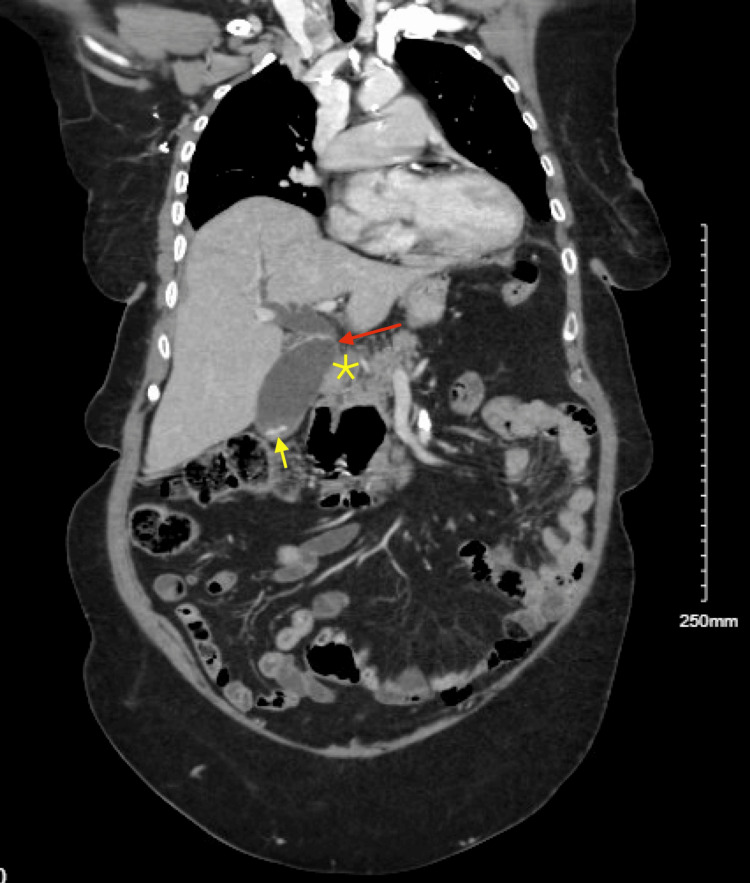

Upon arrival, the patient’s vital signs were stable, with a blood pressure of 161/68 mmHg, a heart rate of 78 beats per minute, a respiratory rate of 18 breaths per minute, and normal oxygen saturation on room air. She was afebrile, and her physical examination was largely unremarkable, with no abdominal tenderness noted. Labs were significant for elevated ALT 175 U/L and AST 134 U/L on presentation; alkaline phosphatase (77 U/L) and total bilirubin (0.3 mg/dL) were within the normal limit. A CT scan of the chest, abdomen, and pelvis with intravenous contrast showed dilation of the biliary and pancreatic ducts, along with findings of choledocholithiasis and a possible obstructive lesion at the head of the pancreas. A large duodenal diverticulum was also observed, encasing the distal portion of the common bile duct and suggesting biliary obstruction (Figures 1, 2). Follow-up imaging with MRI and MRCP confirmed dilation of both intrahepatic and extrahepatic bile ducts, with several filling defects in the common bile duct, consistent with choledocholithiasis, as well as CBD dilation and the presence of a duodenal diverticulum.